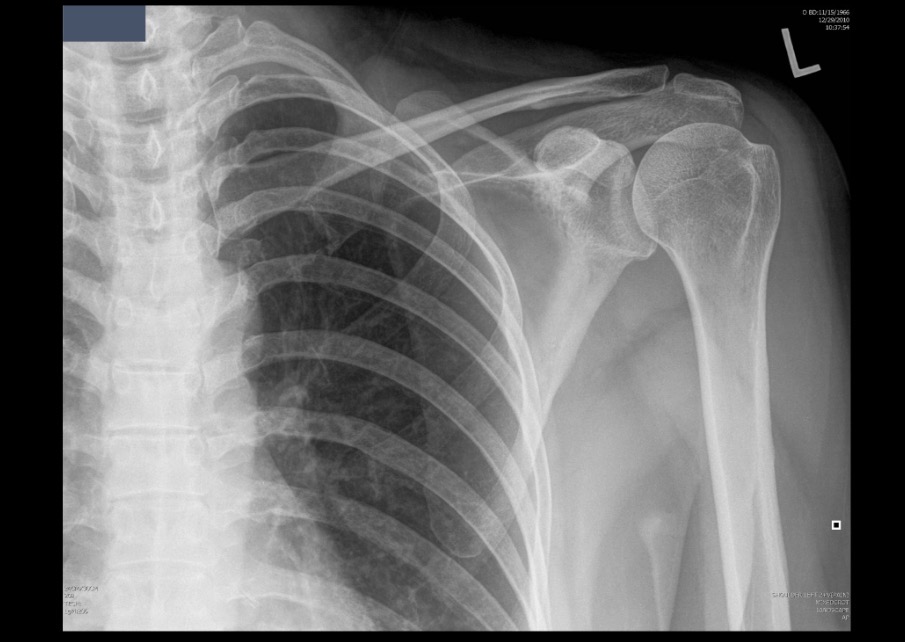

What projection position is this image?

AP Shoulder with External Rotation, Left